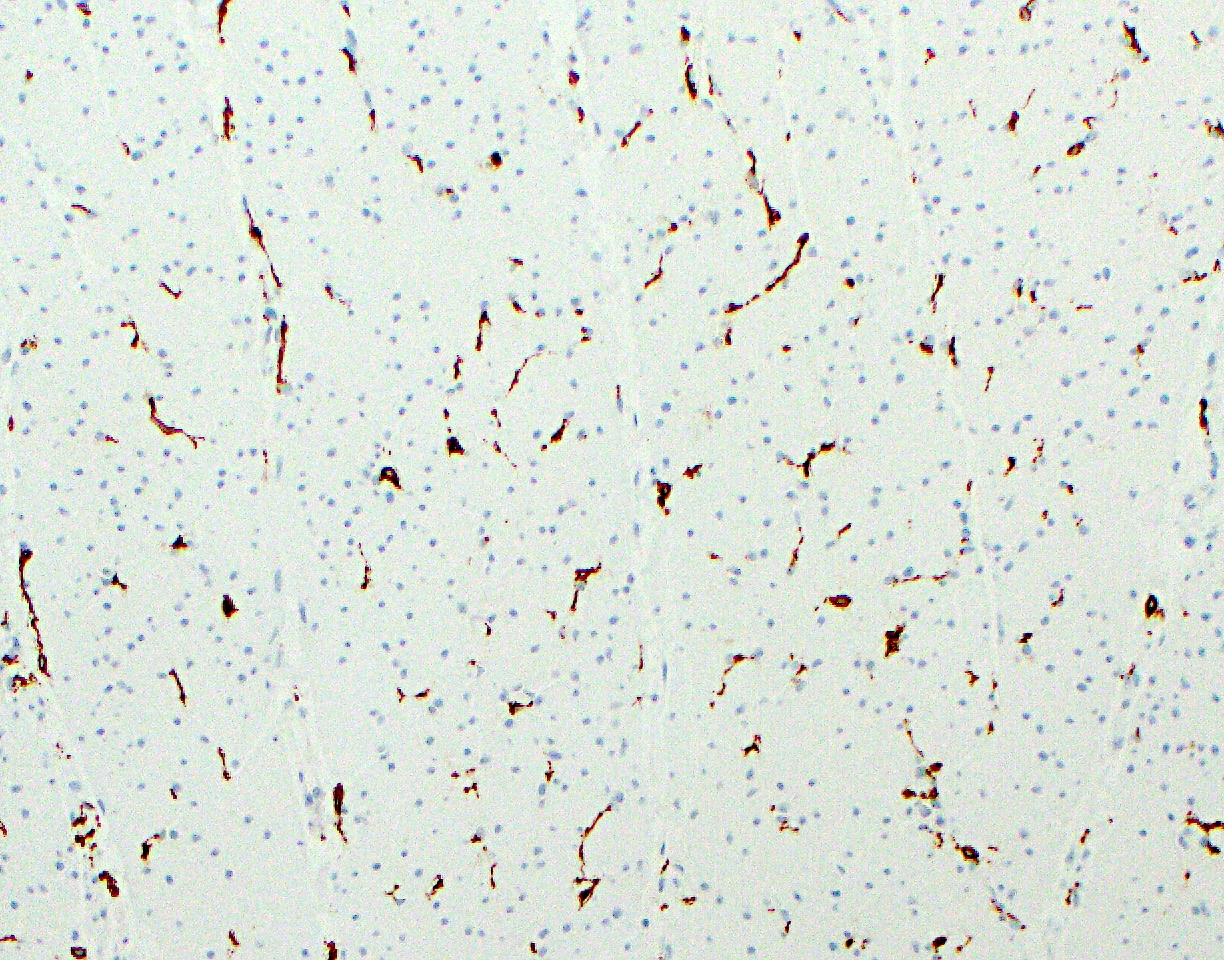

Microscopic (histologic) images

Positive stains

- Enteroendocrine cells: synaptophysin, chromogranin, neuron specific enolase (NSE) and pankeratin AE1 / AE3

- Interstitial cells of Cajal: KIT